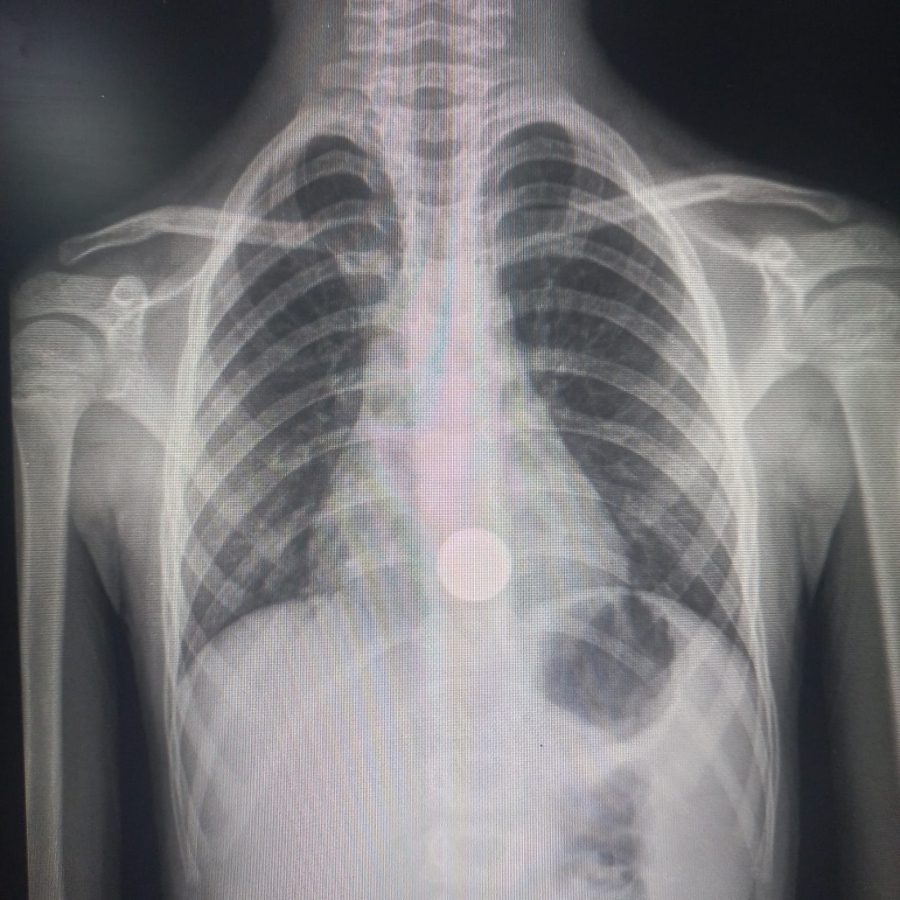

Após avaliação da equipe de saúde, a criança foi transferida para a capital, onde passou por exames mais detalhados. O raio-x confirmou que a moeda está alojada na região do esôfago, exigindo procedimento médico para a retirada do objeto. Até o momento, o paciente permanece sob cuidados especializados, aguardando a extração.